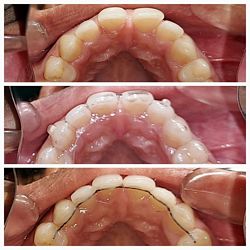

Malocclusion Type: Class I Malocclusion (Re-Treatment) with Spacing in upper and lower anteriors.

Mechanics: Clear Aligner Therapy